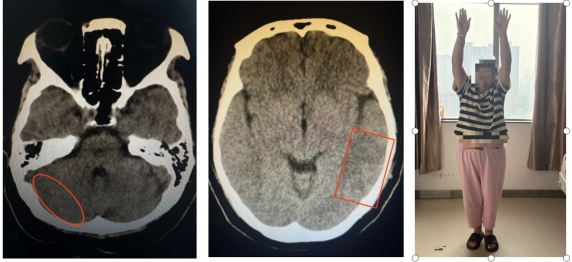

出院前复查CT及患者情况

血栓影消失 血肿吸收 患者完全康复

经过积极治疗,患者症状明显缓解。术后患者进行病因学检查,与风湿免疫科讨论后,考虑患者为狼疮性脑炎。经风湿免疫科抗炎、免疫抑制治疗,患者康复后出院。